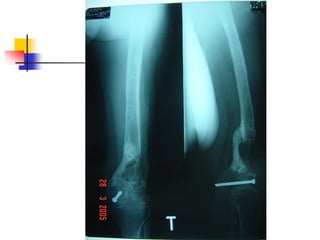

 Xquang : Lúc đầu chưa có dấu hiệu. Về sau

mới có dấu hiệu xương chết, xương tù, phản

ứng màng xương

Dấu hiệu toàn thân không rõ

Lỗ dò , sẹo xấu, xƣơng xù xì

Chi biến dạng, giới hạn khớp

Xquang : xƣơng chết, xƣơng tù, nham nhỡ